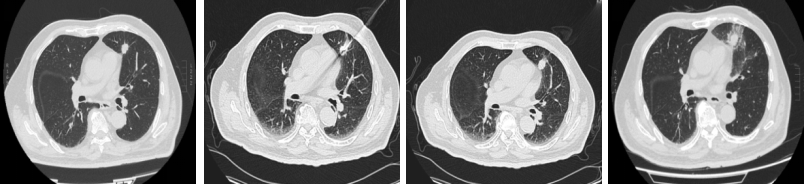

手术全程仅用时35分钟,患者术后安返病房,生命体征稳定。术后复查CT显示:消融区域密度均匀增高,范围完整覆盖靶病灶,周边肺组织、心脏及大血管均未受影响,治疗效果理想。

消融前、消融中、消融中、消融后一天。 受访单位供图